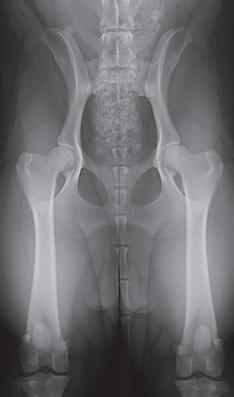

Displasia de cadera (I): etiopatogenia, signos clínicos y pruebas diagnósticas 26